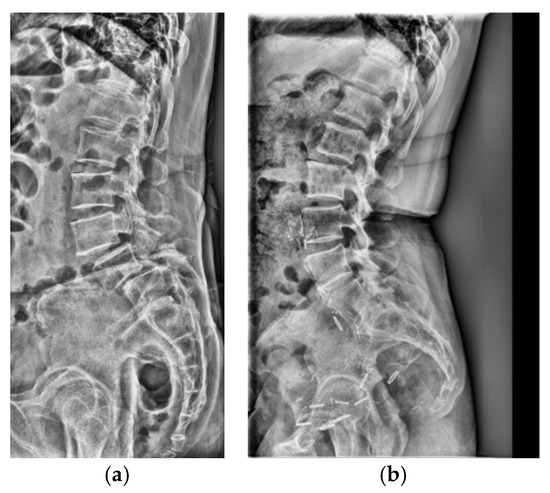

Spinal deformities, including scoliosis, kyphosis, sagittal imbalance, and cervical deformities, remain complex challenges in modern spine surgery. Despite advancements in surgical techniques and imaging modalities, optimizing patient outcomes through precise diagnosis, biomechanical understanding, and innovative treatment strategies is an ongoing endeavor. Recent developments in artificial intelligence (AI) and medical imaging offer new opportunities for refining spinal deformity assessment and enhancing surgical planning.

This Special Issue aims to explore the intersection of biomechanics, imaging, and AI-driven analysis in spinal deformity research, with a particular focus on both spinal and cervical deformities. Topics of interest include, but are not limited to, posture-related spinal and cervical alignment changes, the role of imaging modalities in deformity classification, AI-based phenotyping and prediction models, and novel surgical approaches guided by computational analysis. Contributions integrating clinical, radiographic, and computational methodologies are particularly encouraged.